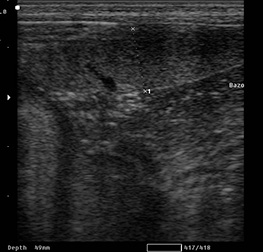

Ecografía de cuello

La ecografía de cuello es una técnica de diagnóstico fácil, rápida e indolora, en donde se evalúan los tejidos blandos del cuello. La base de la lengua, las glándulas salivales, los linfonodulos, la glándula tiroides, la paratiroides, la laringe, la tráquea, el esófago, la vasculatura y los músculos del cuello.

Por lo general, la más indicada, por los endocrinólogos, es la ecografía de la glándula tiroides, (para evaluar la estructura, sus dimensiones y posibles patologías) También las glándulas salivales (en caso de obstrucción de conductos, litiasis), la presencia de cuerpos extraños en base de la lengua y diferentes tipos de tumoraciones en el cuello.